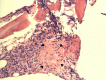

We report a 27-year-old previously healthy man, who presented with fever and painful swelling of both ankles for 6 months, and who had been jaundiced for 1 week. Clinical examination revealed diffuse macular rash, severe pallor, deep icterus, generalised lymphadenopathy and hepatosplenomegaly. Detailed evaluation revealed granulomata in bone marrow aspirate, and numerous acid fast bacilli in lymph node biopsy. Bone marrow PCR was also positive for Mycobacterium tuberculosis. A diagnosis of disseminated tuberculosis was made and antitubercular therapy was initiated. Investigation also showed features of haemophagocytosis within the bone marrow. Results of further tests satisfied the criteria for haemophagocytic lymphohistiocytosis, probably secondary to tuberculosis. However, rapid deterioration in his clinical condition led to his death within 5 days of diagnosis, before appropriate therapy for haemophagocytic lymphohistiocytosis could be instituted. This case report highlights an unusual and deadly presentation of tuberculosis in an immunocompetent individual.